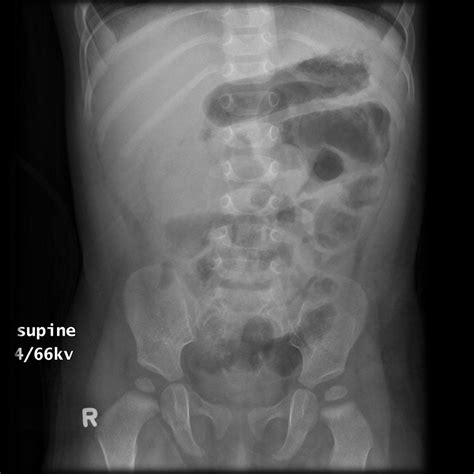

Interpreting Constipation in X-Ray

When interpreting an abdominal X-ray for constipation, radiologists look for several key indicators:

• Fecal Loading: The presence of a large amount of fecal matter in the colon.

• Colonic Dilatation: An enlarged colon, which may indicate chronic constipation.

• Air-Fluid Levels: The presence of air and fluid in the colon, which can suggest obstruction or slow transit.

These findings can help healthcare providers determine the severity of constipation and identify any underlying issues that may be contributing to the condition.